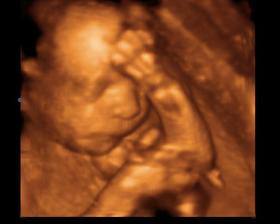

Baby 🙂

Tak uz som tu, narodil som sa 23.2.2008, s mierami 2800g a 48 cm, bol som malicky, ale vsetko dobehnem.